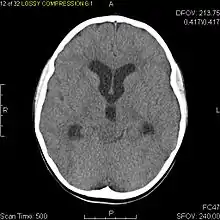

Pilocytic astrocytomas are often cystic, and, if solid, tend to be well-circumscribed. They are characteristically easily seen on computed tomography (CT scans) and magnetic resonance imaging (MRI).

Usually – depending on the interview of the patient and after a clinical exam which includes a neurological exam and an ophthalmological exam – a CT scan and/or an MRI scan will be performed. A special dye may be injected into a vein before these scans to provide contrast and make tumors easier to identify. The neoplasm will be clearly visible.

Visual aspect

Microscopically, an astrocytoma is a mass that looks well-circumscribed and has a large cyst. The neoplasm may also be solid.